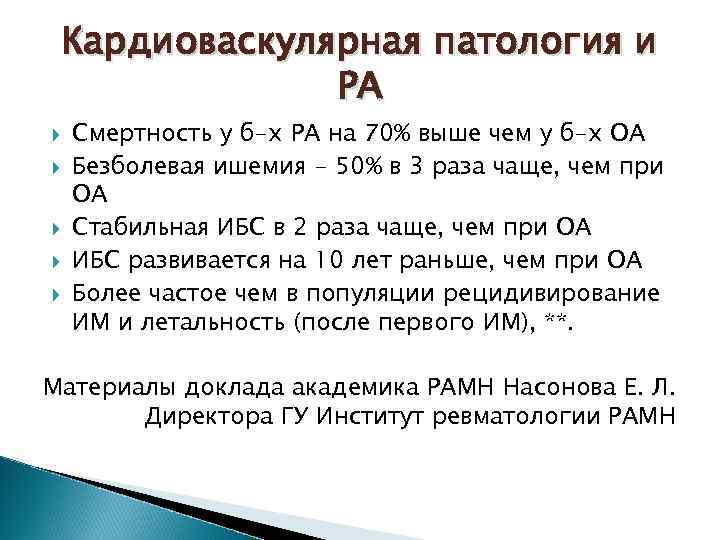

Кардиоваскулярная патология и РА Смертность у б-х РА на 70% выше чем у б-х ОА Безболевая ишемия - 50% в 3 раза чаще, чем при ОА Стабильная ИБС в 2 раза чаще, чем при ОА ИБС развивается на 10 лет раньше, чем при ОА Более частое чем в популяции рецидивирование ИМ и летальность (после первого ИМ), **. Материалы доклада академика РАМН Насонова Е. Л. Директора ГУ Институт ревматологии РАМН